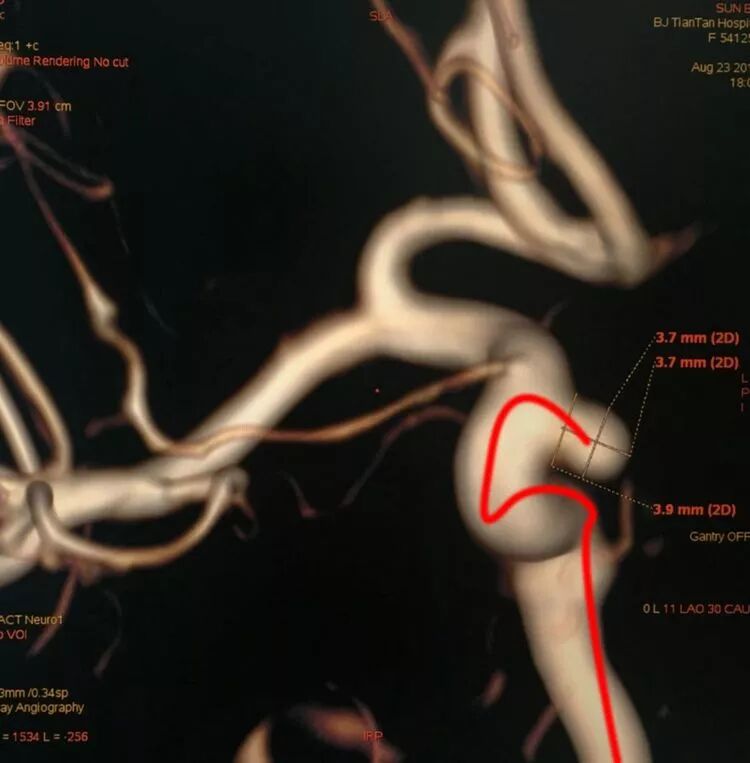

前交通动脉瘤,朝向上方生长,微导管头端塑反向两个弯儿(绿圆圈)呈S形

病例2

另外一例前交通动脉瘤,微导管头端同上塑反向两个弯儿(绿圆圈)呈S形